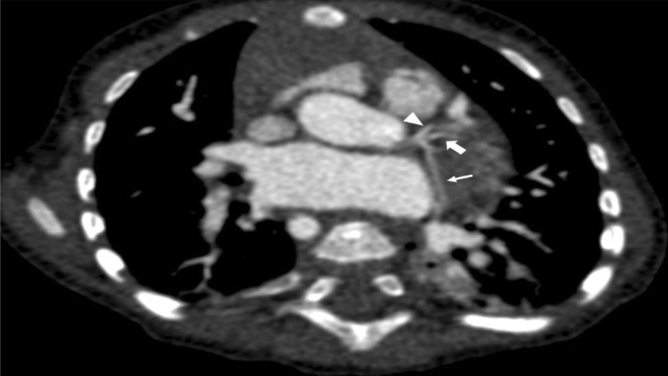

Figure 3.

Double angulated reconstruction demonstrating a trifurcation of the left main coronary artery giving rise to the left anterior descending artery (arrowhead), a left median branch (thick arrow), and the left circumflex artery (thin arrow) in a 5-month-old female infant with a tetralogy of Fallot.